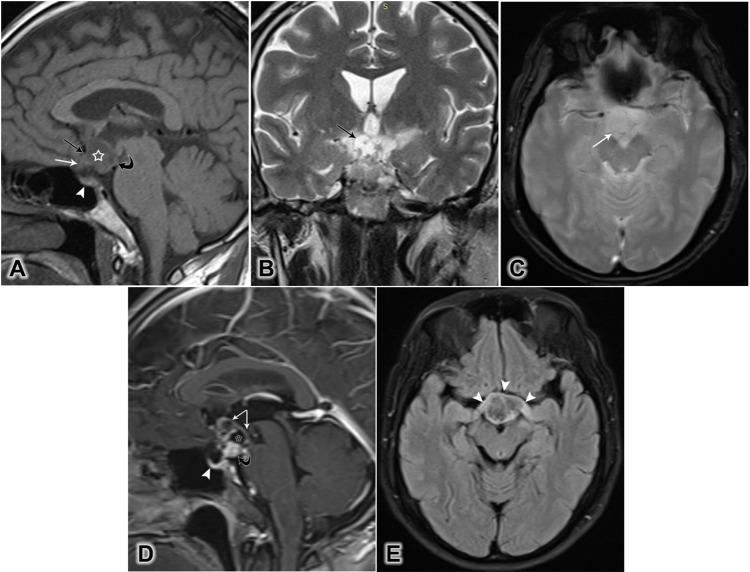

We aimed to describe the magnetic resonance imaging features observed in five cases of strictly intrinsic third ventricular papillary craniopharyngiomas, including two cases of mixed cystic and solid tumors and three cases of pure solid masses.

我们旨在描述5例严格意义上的第三脑室内乳头状颅咽管瘤的磁共振成像特征,其中包括2例囊实性混合肿瘤和3例纯实性肿块。